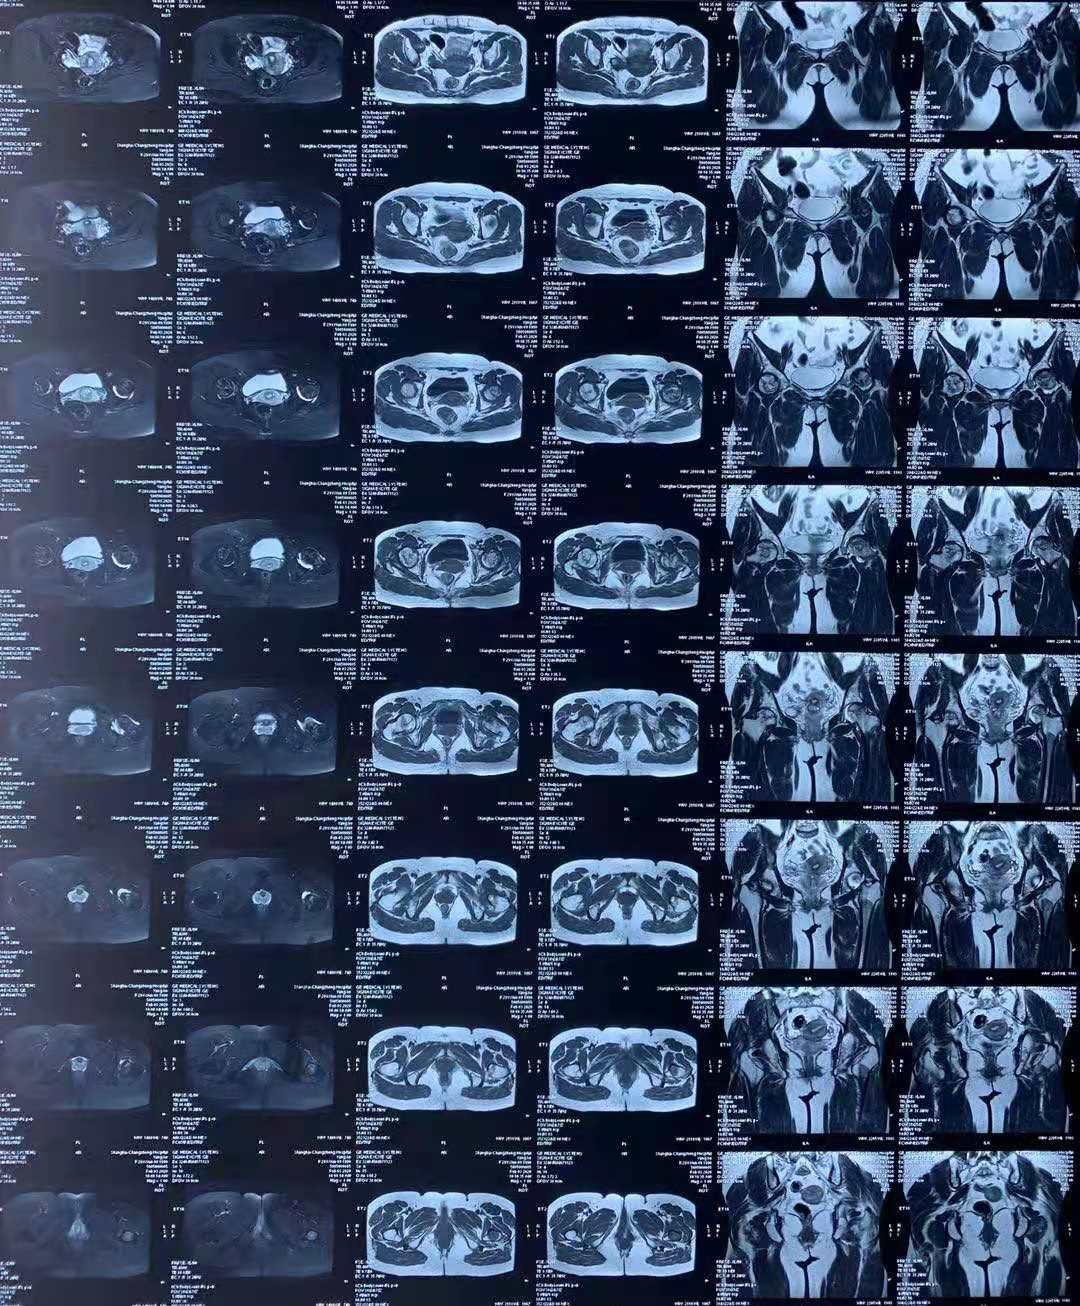

有酗酒习惯、长期应用激素的人群,如果感觉到髋部疼痛不适,要警惕股骨头坏死。影像学检查有助于确诊,MRI对早期坏死敏感,X线主要用于观察髋关节大体情况。

Ⅰ期:髋部隐痛不适,X线和CT检查正常,MR可以看到股骨头内部已经开始发生细小变化。

Ⅱ期:走路时的痛感明显,X线片可见股骨头有些硬化或囊变,但股骨头的形态还比较圆,没有塌陷。此期可持续1~2年。

Ⅲ期:疼痛加重,甚至躺着也疼,活动时疼痛剧烈。X线检查股骨头先变平,而后最终塌陷。